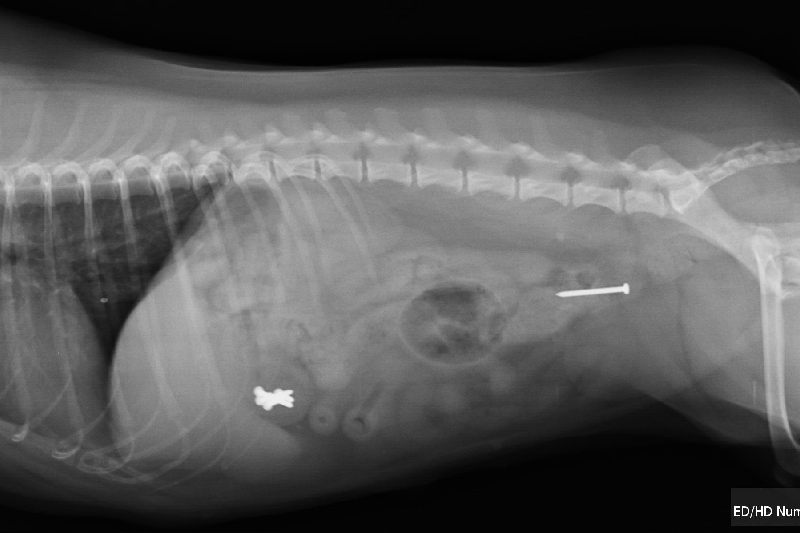

I then took Clarice to the vet for an Xray which revealed 6 nails stuck inside her stomach and 1 somehow luckily on its way out. The option to leave then in her stomach and hope for a safe exit is too risky due to the sharp nails possibly puncturing holes inside her body. Surgery is the only reasonable option.